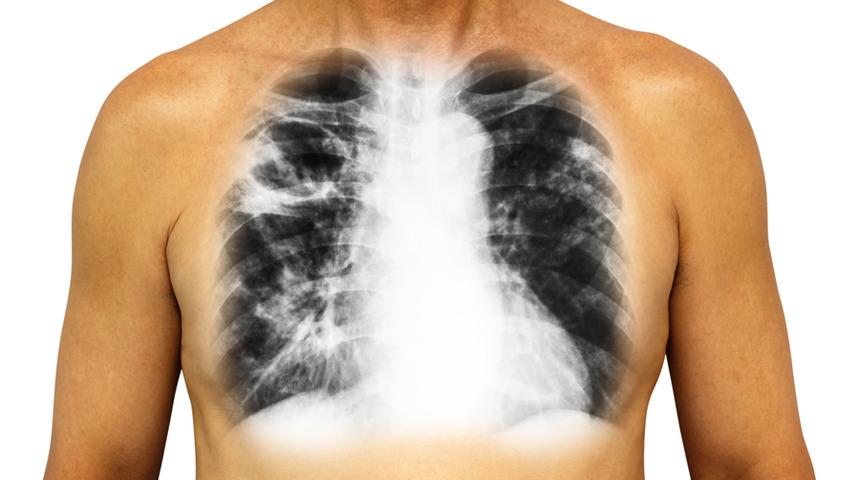

Kronik Obstrüktif Akciğer Hastalığı yani yaygın olarak bilinen şekliyle KOAH dünya genelinde en sık ölümlere neden olan hastalıklar arasında dördüncü sırada yer alıyor. 2020 yılında ise üçüncü sıraya yükselmesi bekleniyor. 21 Kasım Dünya KOAH Günü’nde yapılan bilgilendirmelerle farkındalık yaratılmak istenen KOAH hastalığı sadece 2012 yılında 3 milyon insanın ölümüne neden oldu. Bu nedenle KOAH tedavisi geç kalınmadan başlanması gereken hastalıklar arasında yer alıyor. İşte detaylar...

KOAH için, başta sigara olmak üzere tütün ve tütün mamullerinin kullanılması en büyük risk faktörü olarak başı çekiyor. Zararlı gaz ve partikül maruziyeti sonucu akciğerlerde kalıcı olarak hava akımı kısıtlılığı gelişiyor. Nefes darlığı, balgamlı veya balgamsız öksürük gibi belirtilerle kendini gösteren KOAH, alevlenme olarak tabir edilen akciğer fonksiyonlarında ve hastanın genel durumunda ani olarak meydana gelen kötüleşmeler ile seyreden uzun süreli bir hastalık. Alevlenmeler hastanın tedavisi ve hastalığın gidişatı için olumsuz etki yaratabiliyor.